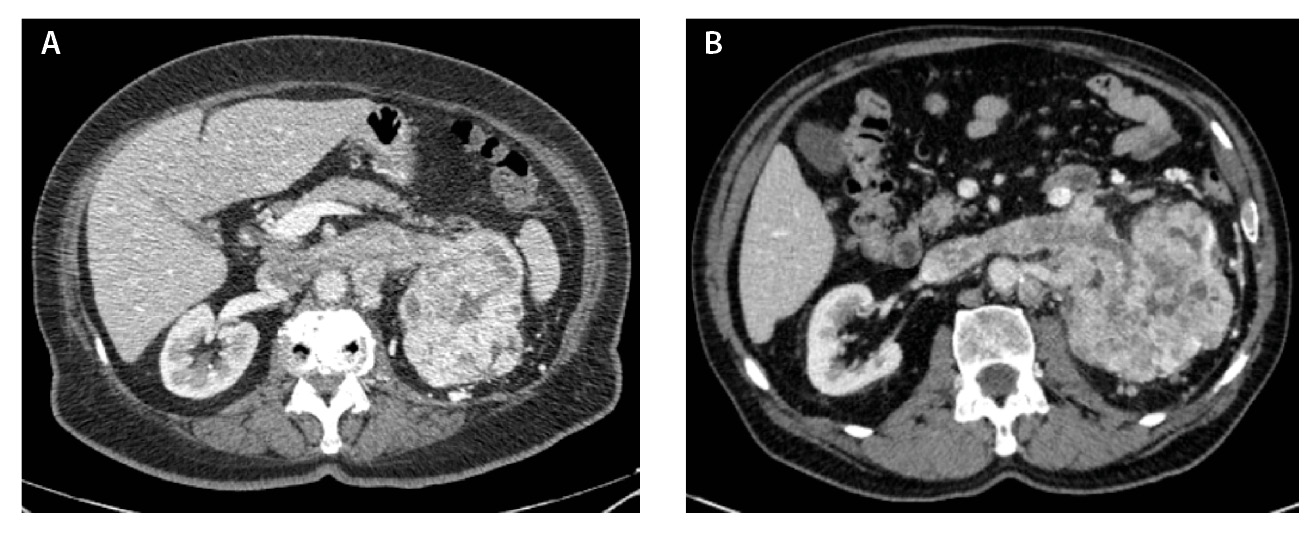

Компьютерная томография (КТ) с внутривенным контрастным усилением широко используется как метод диагностики и первичного стадирования скПКР. В настоящее время наиболее значимыми характеристиками опухоли для предоперационного стадирования и планирования хирургического лечения скПКР признаны расположение, размер опухоли и признаки ее инвазивного роста [3–6], а структура и характер контрастирования позволяют дифференцировать типы ПКР, но ни один из этих показателей не дает возможности достоверно прогнозировать степень дифференцировки опухоли. Структура скПКР любой степени дифференцировки, как правило, гетерогенная с наличием солидного и кистозного компонентов. Признаки инвазивного роста опухоли, наличие метастазов позволяют предположить низкую степень дифференцировки опухоли, однако не являются достоверными признаками. Как видно на рис. 1, скПКР разной степени дифференцировки по данным КТ выглядят практически идентично: в обоих случаях визуализируется опухолевый тромб в почечной вене с распространением в просвет нижней полой вены. Такие характеристики, как размер опухоли, пофазное накопление контрастного вещества и градиент накопления контрастного вещества при КТ-исследовании, также не являются строго специфичными для разных степеней дифференцировки скПКР (рис. 2).

Рис. 1. Светлоклеточный почечно-клеточный рак: А – Grade 4 (данные компьютерной томографии пациентки Б.), Б – Grade 2 (данные компьютерной томографии пациента Г.). На обоих снимках кортико-медуллярная фаза исследования: гиперваскулярная опухоль солидно-кистозного строения, замещающая паренхиму левой почки, опухолевый тромб в просвете левой почечной вены с распространением в нижнюю полую вену; метастически измененный регионарный лимфатический узел